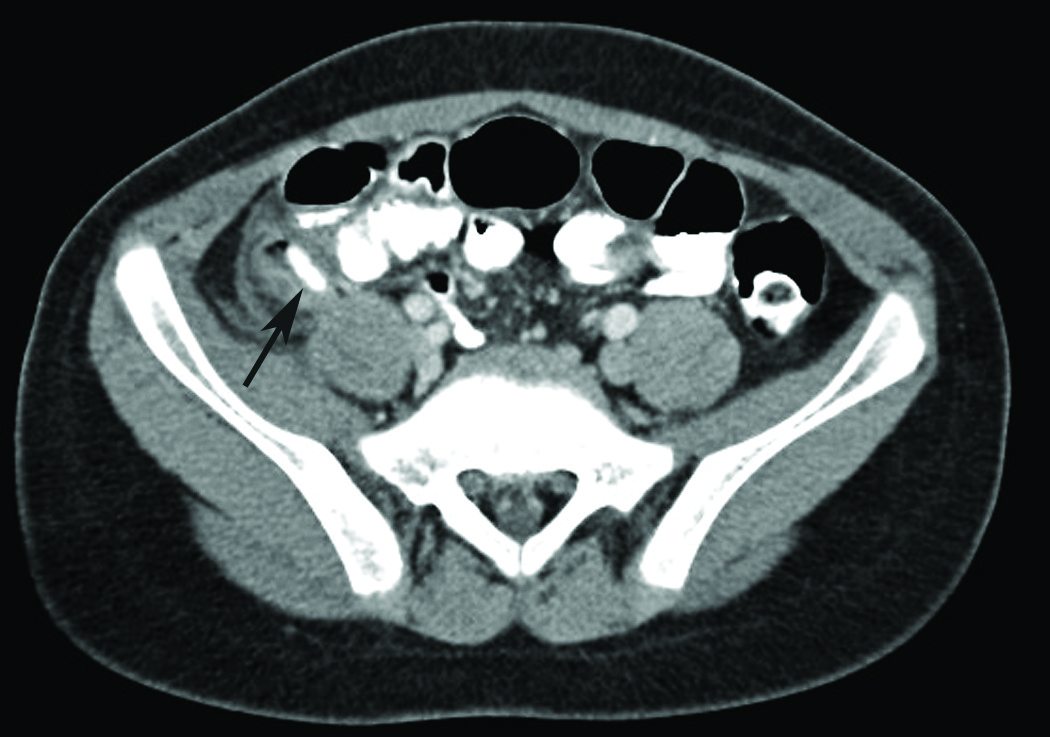

David Effron, MD; Maya C. Myslenski, MD

<p><img src="/sites/default/files/transfer/axial_ct_appendicitis_figure_1.jpg" width="115" height="115" style="margin: 5px; float: left;">An 8-year-old...